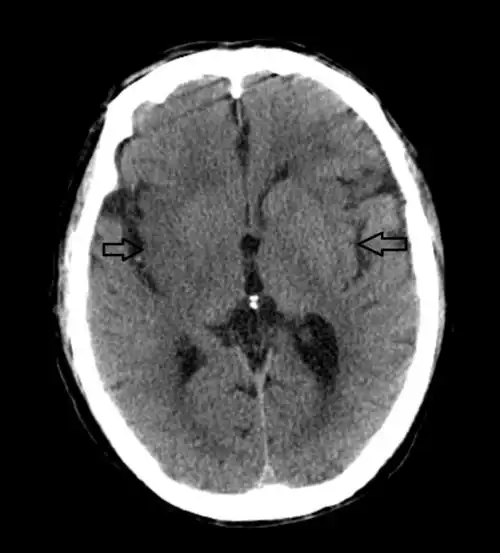

67超急性期大面积脑梗死ct平扫表现

行颅脑ct平扫(可点击图片放大查看)

通过ct平扫和核磁t2及flair像,均发现病灶显示不是很明显,容易造成漏